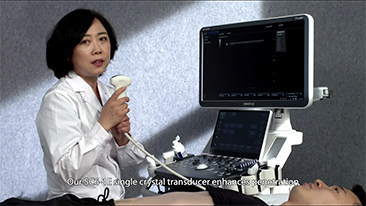

We work closely with our customers so our products and systems meet evolving clinical needs. Mindray aims to provide you with comprehensive imaging solutions for more precise diagnosis and confident treatment in different applications.

Ultra-wide non-linear UWN+ contrast imaging technology provides better penetration, higher contrast-tissue ratio, with lower MI and longer perfusion time observation.

Using ultrasound as part of an optimised OBG workflow can support large patient volumes for women's health screening. For example, central nervous system (CNS) malformations are one of the most common congenital abnormalities. Due to imaging conditions such as poor fetal position, the median sagittal plane (MSP) is particularly difficult to obtain from 2D ultrasound. Therefore, automated detection and measurements can greatly enhance scanning efficiency.